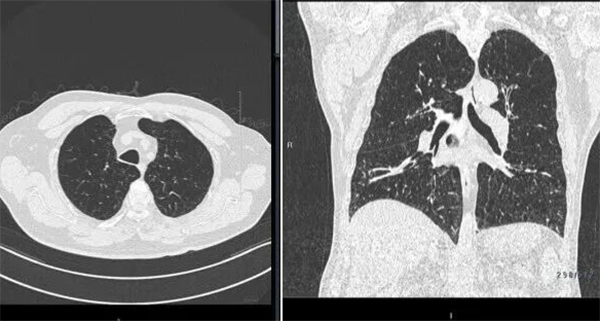

(肺部CT呈现非均质肺气肿表现)

由于患者属于典型的非均质上肺肺气肿,双肺上叶多个肺段均需干预。术前,呼吸与危重症医学科(二)团队结合胸部CT与虚拟导航技术,对目标亚段支气管进行了细致的可及性及热剂量评估,精准规划出最优手术路径。